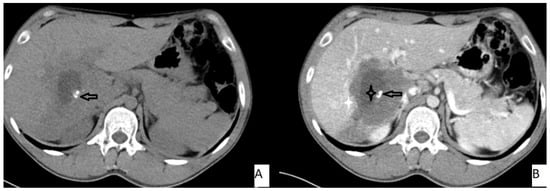

The most frequently encountered CT pattern was a heterogeneous mass with calcifications and hypoattenuating areas (72.3%). Most of the lesions had irregular contours (85.4%), 85.4% lacked contrast enhancement, 77.4% of the lesions had calcifications, and atrophy and capsular retraction was present in 10.7% of the lesions (Figure 2 and Figure 3). Table 3 details the distribution of CT appearances.

Figure 2.

51-year-old male. Hepatic lesion with irregular contours and calcifications on precontrast axial CT (A). On portal venous images (B), no enhancement is present in the lesion. Central necrosis can be seen (A,B—black star). Perilesional enhancement (B—white star) and capsular (A,B—arrows) retraction are present.

Figure 3.

53-year-old female. Hepatic lesion with irregular borders and calcification (A,B—arrows) on precontrast axial CT (A). On portal venous images (B), no enhancement is present in the lesion. Central necrosis can be seen (B—black star). Perilesional enhancement (B—white star) is present.